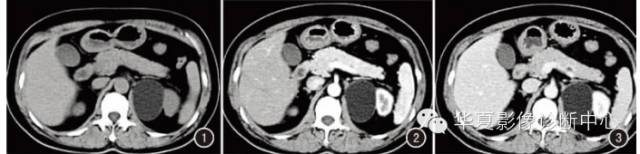

例2女,40岁。体检发现右肾上腺占位性病变。体检:双肾区无叩击痛,余无特殊。实验室检查亦未见异常。B超:右肾上腺区探及大小约18mm×16mm囊性暗区,侧壁有强回声,边界清。CT示:右肾上腺区一结节状低密度影,直径约16mm,密度不均匀,其内见不规则钙化灶,轮廓清晰(图6),增强扫描囊壁及间隔轻度强化(图7、8)。

图6~8例2。CT平扫(图6)右肾上腺结节状低密度影,密度不均匀,边缘见不规则钙化灶。增强扫描静脉期(图7、8)囊壁及间隔轻度强化。